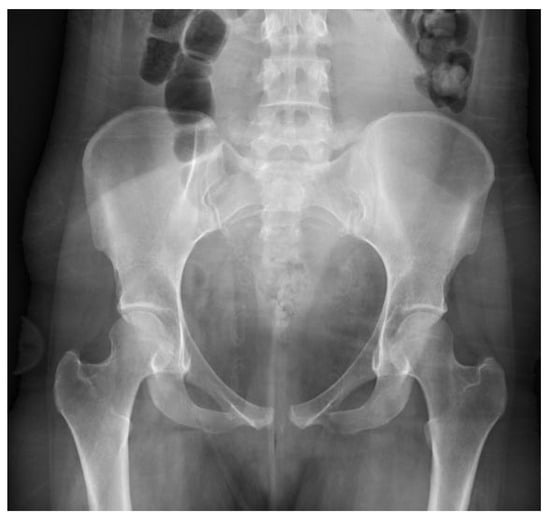

On hospital day five, the patient was hemodynamically stable with sufficient pain control, and she was discharged home with instructions to wear her binder as much as possible, aside from hygiene activities, and to limit her activities to avoid running, jumping, prolonged walking, and high-impact activities. At 3 weeks post-injury, pelvic radiographs demonstrated largely maintained alignment of the pubic symphysis with some mild increase in diastasis to 1.9 cm, and her pain was well managed via acetaminophen taken only at night (Figure 3). She was instructed to wean her binder use gradually beginning at 6 weeks post-injury. At 3 months post-injury, her pain had resolved, and her pelvic imaging continued to show maintained alignment at 1.9 cm(Figure 3). She was advanced to activity as tolerated. At her six-month follow-up, she was ambulating without restriction, including running, jumping, and playing competitive sports, with radiographic diastasis again measuring 1.9 cm (Figure 3).

Figure 3. Follow-up AP pelvis radiographs (a) 3-week post-injury AP pelvis radiograph; (b) 3-month post-injury AP pelvis radiograph; (c) 6-month post-injury AP pelvis radiograph.